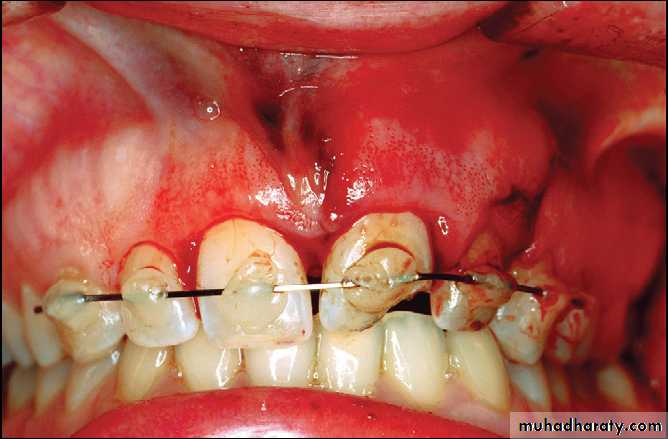

Platally displaced central and lateral incisors in apically mature tooth.

Position of teeth after digital reduction and stabilization with bonded arch wire.- Intrusion

Fixation by wiring

Composite and orthodontic wire splint